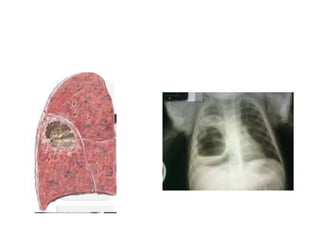

3. PATRÓN DESTRUCTIVO

1. Cavidades de pared gruesa: abscesos

2. Cavidades de pared fina: histiocitosis

3. Bullas enfisema

Caverna por TBC

Quiste Hidatidico

Bula pulmonar